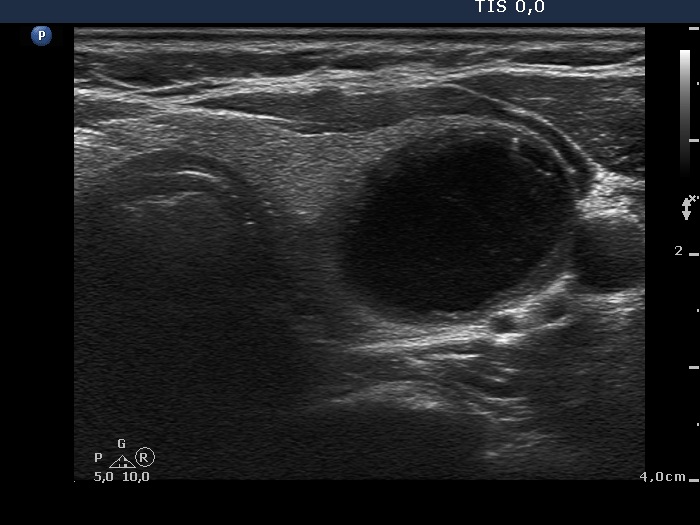

Ultrasonography. The thyroid was echonormal. There was a minimally-moderately hypoechogenic nodule in the right while a cystic nodule in the left lobe. There were numerous hyperechogenic figures both in the cystic and in the lower solid part of the lesion. The lesion presented no vascularization.

Comment. The presentation of the bright hyperechogenic granules are relatively unusual, they were mostly located within the solid part causing a false impression of starry sky phenomenon. In fact, they were comet-tail artifacts.